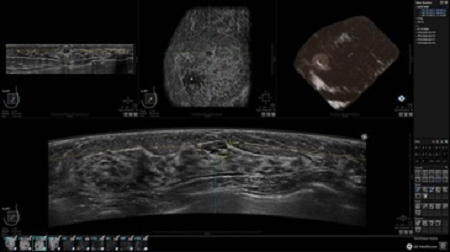

GE INVENIA ABUS – это современный УЗИ аппарат, который создан для точной и эффективной диагностики сканирования с высокой плотностью молочных желез. Выявляемость патологий раковых и предраковых стадий заболевания составляет 55%, что в конечном счете позволяет ставить врачу точные и своевременные диагнозы. Традиционные методы использования маммографии не показывают такой выявляемости, ограничиваясь лишь 3-38%.

УЗИ-аппарат GE INVENIA ABUS позволяет проводить максимально операторонезависимые процедуры, что значительно снижает риск неправильной постановки диагноза и сопутствующие издержки на обработку информации. Система готовит отчет в течение 3-х минут после сканирования, это безусловное преимущество по сравнению с обычным УЗИ сканером.

• Получение объемных 3D изображений с возможностью покадрового просмотра

• Алгоритмы обработки изображений: алгоритм однородности изображения ткани (TEA), подавление зернистости, компенсация акустической тени от соска (NSC), определение границ молочной железы (BBD), определение стенки грудной клетки

• Отображение объемных 3D ультразвуковых изображений, которые состоят из традиционных поперечных и воссозданных коронарных и сагиттальных проекций

• Многооконный просмотр: 4 - 12 изображений

• Стандартизованная ориентация изображения: «толстый срез» в коронарной плоскости; поперечная; сагиттальная плоскость; радиальный и антирадиальный поворот изображения; просмотр исключительно области интереса

• 360 ° APC - отображение области по «любой точке компаса»